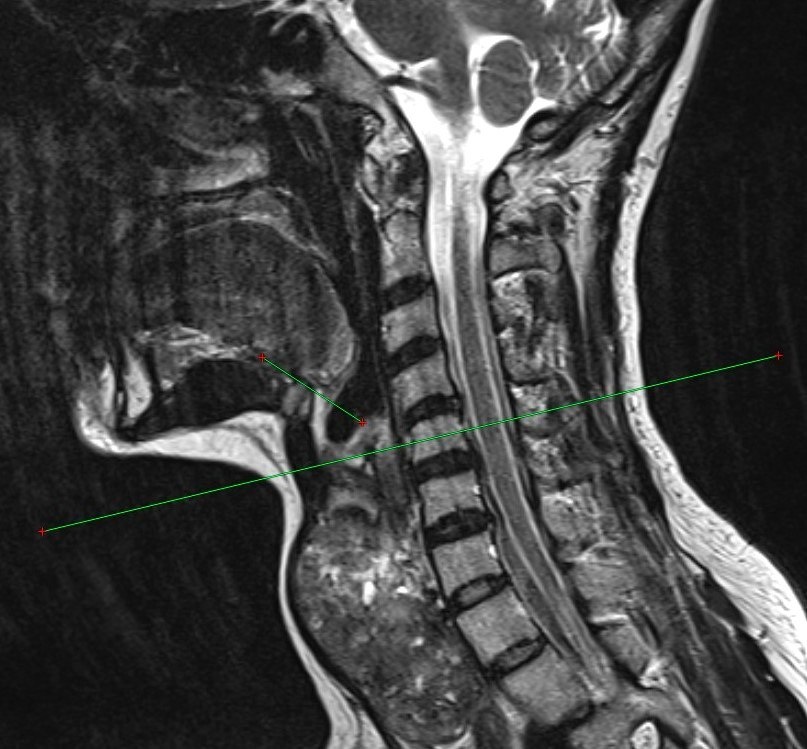

Коллектив Оренбургского государственного медицинского университета, включая доцента Арину Жирнову и профессора Сергея Лященко, разработал и запатентовал способ перевязки верхнего полюса щитовидной железы при её увеличении. Метод учитывает толщину и расположение верхнего полюса органа, снижает риск кровотечения и повреждения верхнего гортанного нерва. Преимущества новой методики – простота и возможность применения в любом стационаре с томографом. Фото: ОрГМУ

Коллектив Оренбургского государственного медицинского университета, включая доцента Арину Жирнову и профессора Сергея Лященко, разработал и запатентовал способ перевязки верхнего полюса щитовидной железы при её увеличении.

Метод учитывает толщину и расположение верхнего полюса органа, снижает риск кровотечения и повреждения верхнего гортанного нерва.

Преимущества новой методики – простота и возможность применения в любом стационаре с томографом.

Фото: ОрГМУ